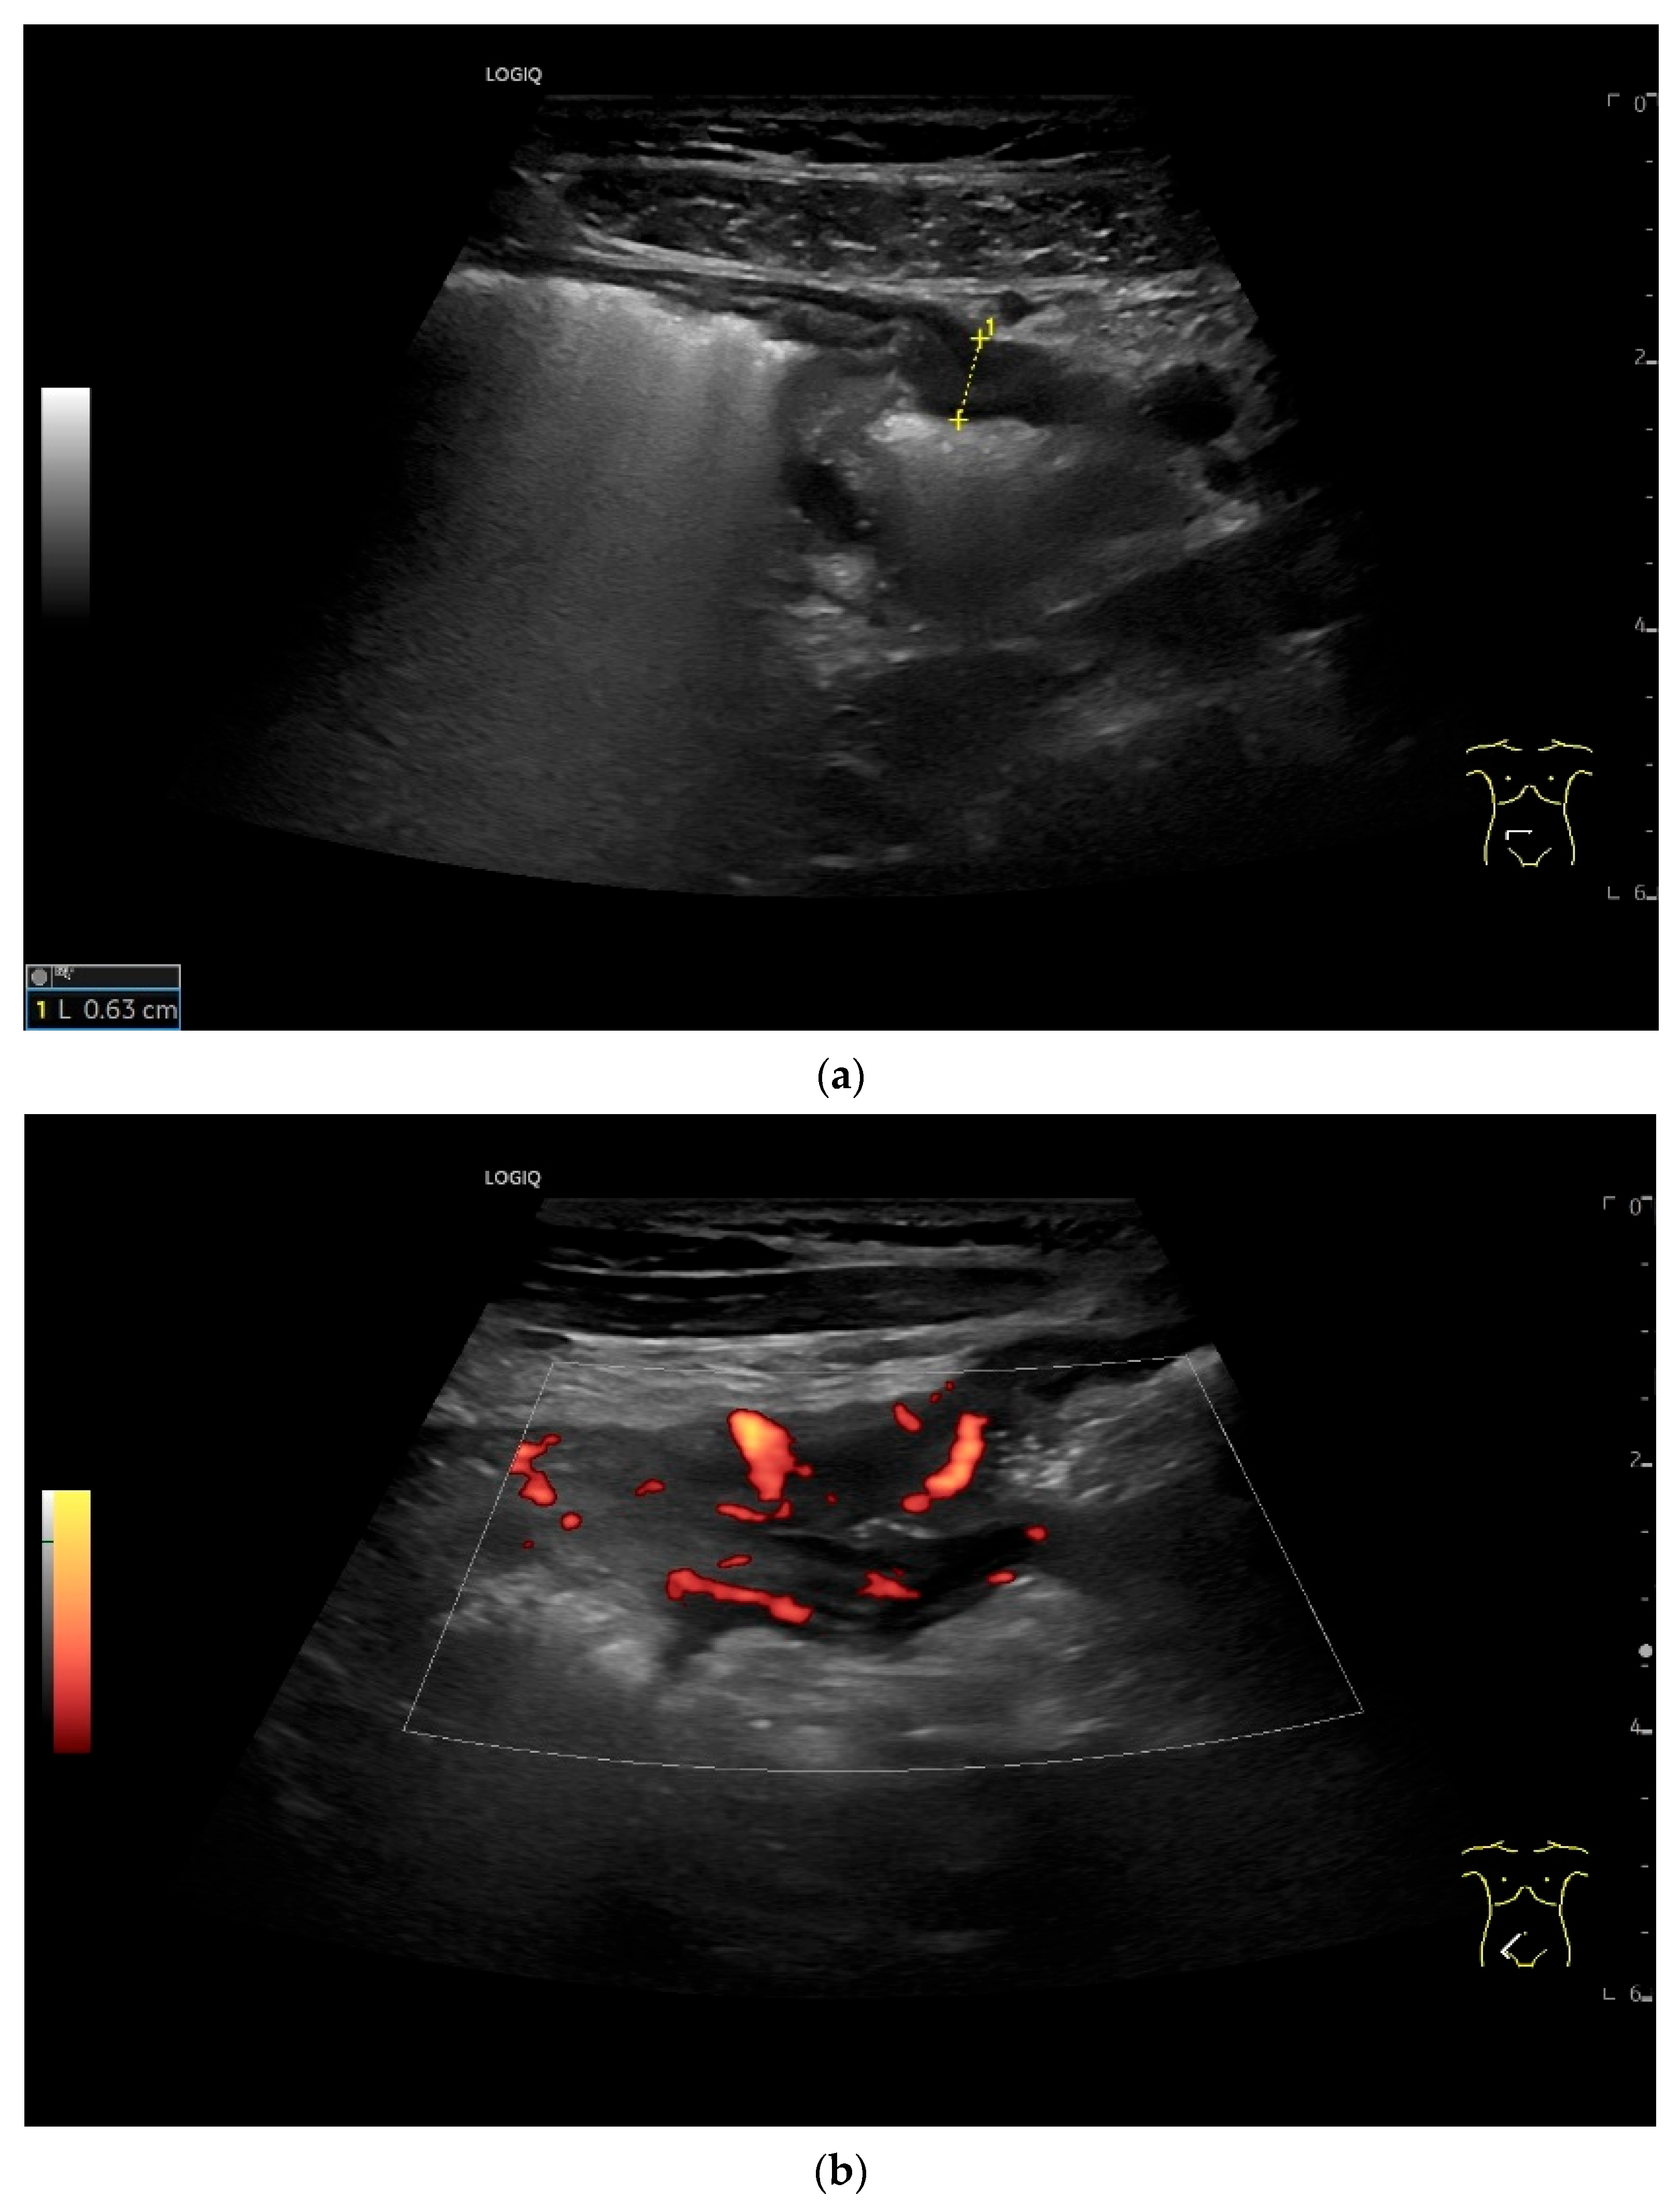

| Neuroendocrine tumor | Small, nodular hypoechoic wall thickenings, mostly in the submucosa with spreading into the other layers. Usually with small vessels on CDI. Regionally enlarged lymph nodes. Multilocular manifestations are possible. |

| GIST | Round hypoechoic masses, homogeneous or heterogeneous depending on size. They usually originate from the muscularis propria, which can be difficult to distinguish in US. Small vessels on CDI, hyperenhancement on CEUS. They move with the small intestine and can change position. |